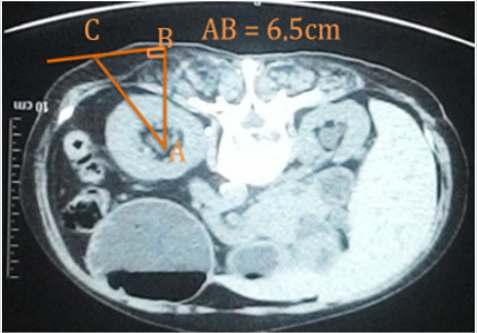

All patients had had the CT-scan. We were choiced the position (in the collecting system), this position had called A point. We continue choiced the B point on the back (figure 1) and measure the AB by the ruler on the CT-scan. After that, choice the C point, how CB and pelvis are straight (figure 2). Then we measure the CB on the real patient skin. Based on the Pythagore principle in the right triangle, we calculated the length of CA and the degree of ACB corner (figure 3).